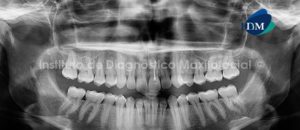

Paciente de sexo masculino de 21 años de edad acude a la consulta radiológica para la evaluación preoperatoria a la extracción de las terceros molares inferiores.